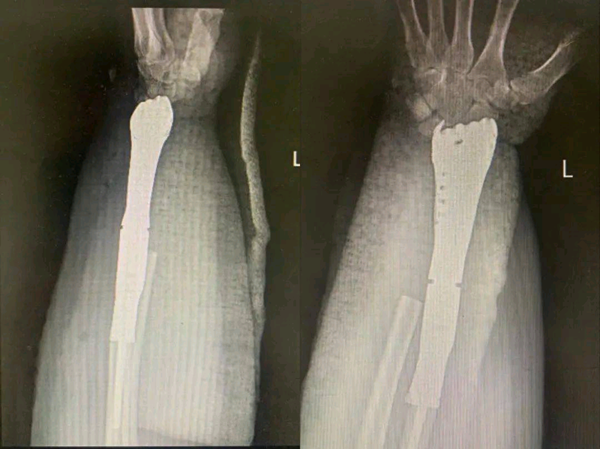

△術(shù)后X線片

術(shù)前骨二科醫(yī)生先設(shè)計出假體草圖,同工程師反復溝通后,進行個性化手術(shù)方案設(shè)計。通過CT等影像學檢查采集了橈骨形態(tài)數(shù)據(jù),用3D打印技術(shù)制作了患側(cè)腕關(guān)節(jié)假體,成功實施既定的手術(shù)方案。假體的設(shè)計充分體現(xiàn)了醫(yī)工結(jié)合的個體化設(shè)計理念。

△術(shù)前X線片